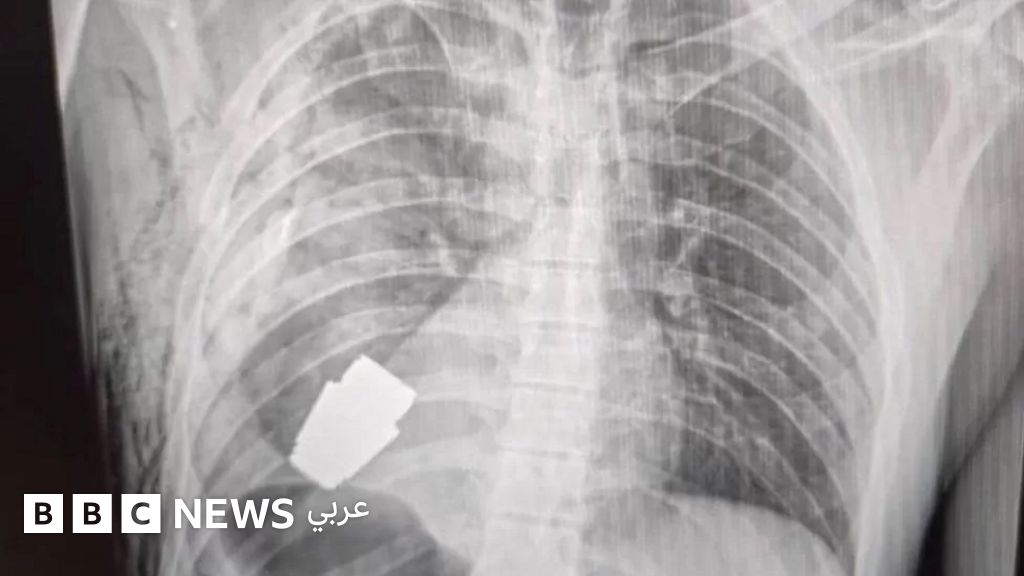

أزيلت قنبلة يدوية غير منفجرة من صدر جندي أوكراني.

ونشرت صور قبل الجراحة وبعدها على صفحة فيسبوك للخدمات الطبية للقوات المسلحة الأوكرانية. وتظهر صورة بالأشعة السينية القنبلة بالقرب من قلب الجندي، وتظهر أخرى جراحاً وهو يحمل العبوة المميتة.

وأعلنت الخدمات الطبية أن الجراحة أجريت من دون استخدام التخثير الكهربي - وهي طريقة شائعة يستخدم فيها تيار كهربائي للمساعدة بالسيطرة على النزيف أثناء الجراحة - لأن "العبوة يمكن أن تنفجر في أي وقت".

وأضافت أن العبوة عبارة عن قنبلة من نوع "في أو جي"، وهي قطعة ذخيرة بطول 4 سم تطلق من قاذفة قنابل يدوية، ويمكنها قطع مسافة 400 متر تقريباً، ومصممة للانفجار فوق الأرض مباشرة.